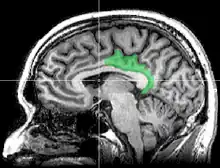

Cortex cingulaire postérieur

Le cortex cingulaire postérieur (CCP) est, dans le cerveau, une zone à l'arrière du cortex cingulaire ressemblant à une ceinture entourant le corps calleux.

La description du cortex cingulaire en une zone antérieure et une postérieure a été faite par Korbinian Brodmann en 1909 sur la base d'une différence anatomique et dans l'ignorance de leurs fonctions. Dans cet ancien découpage, le cortex cingulaire postérieur (CCP) consiste dans les aires de Brodmann 29, 30, 23, 31, et assure des fonctions évaluatives selon Brent Alan Vogt[1] (1992).

- cortex cingulaire postérieur CCP, avec le même nom mais limité aux aires 23 et 31

- cortex rétrosplénial CRS, regroupant les aires 29 et 30. Il entoure directement le splenium du corps calleux.

Pour éviter les confusions, Brent A. Vogt appelle l'ensemble formé par le cortex cingulaire postérieur (CCP) et le cortex rétrosplénial (CRS), le gyrus cingulaire postérieur.